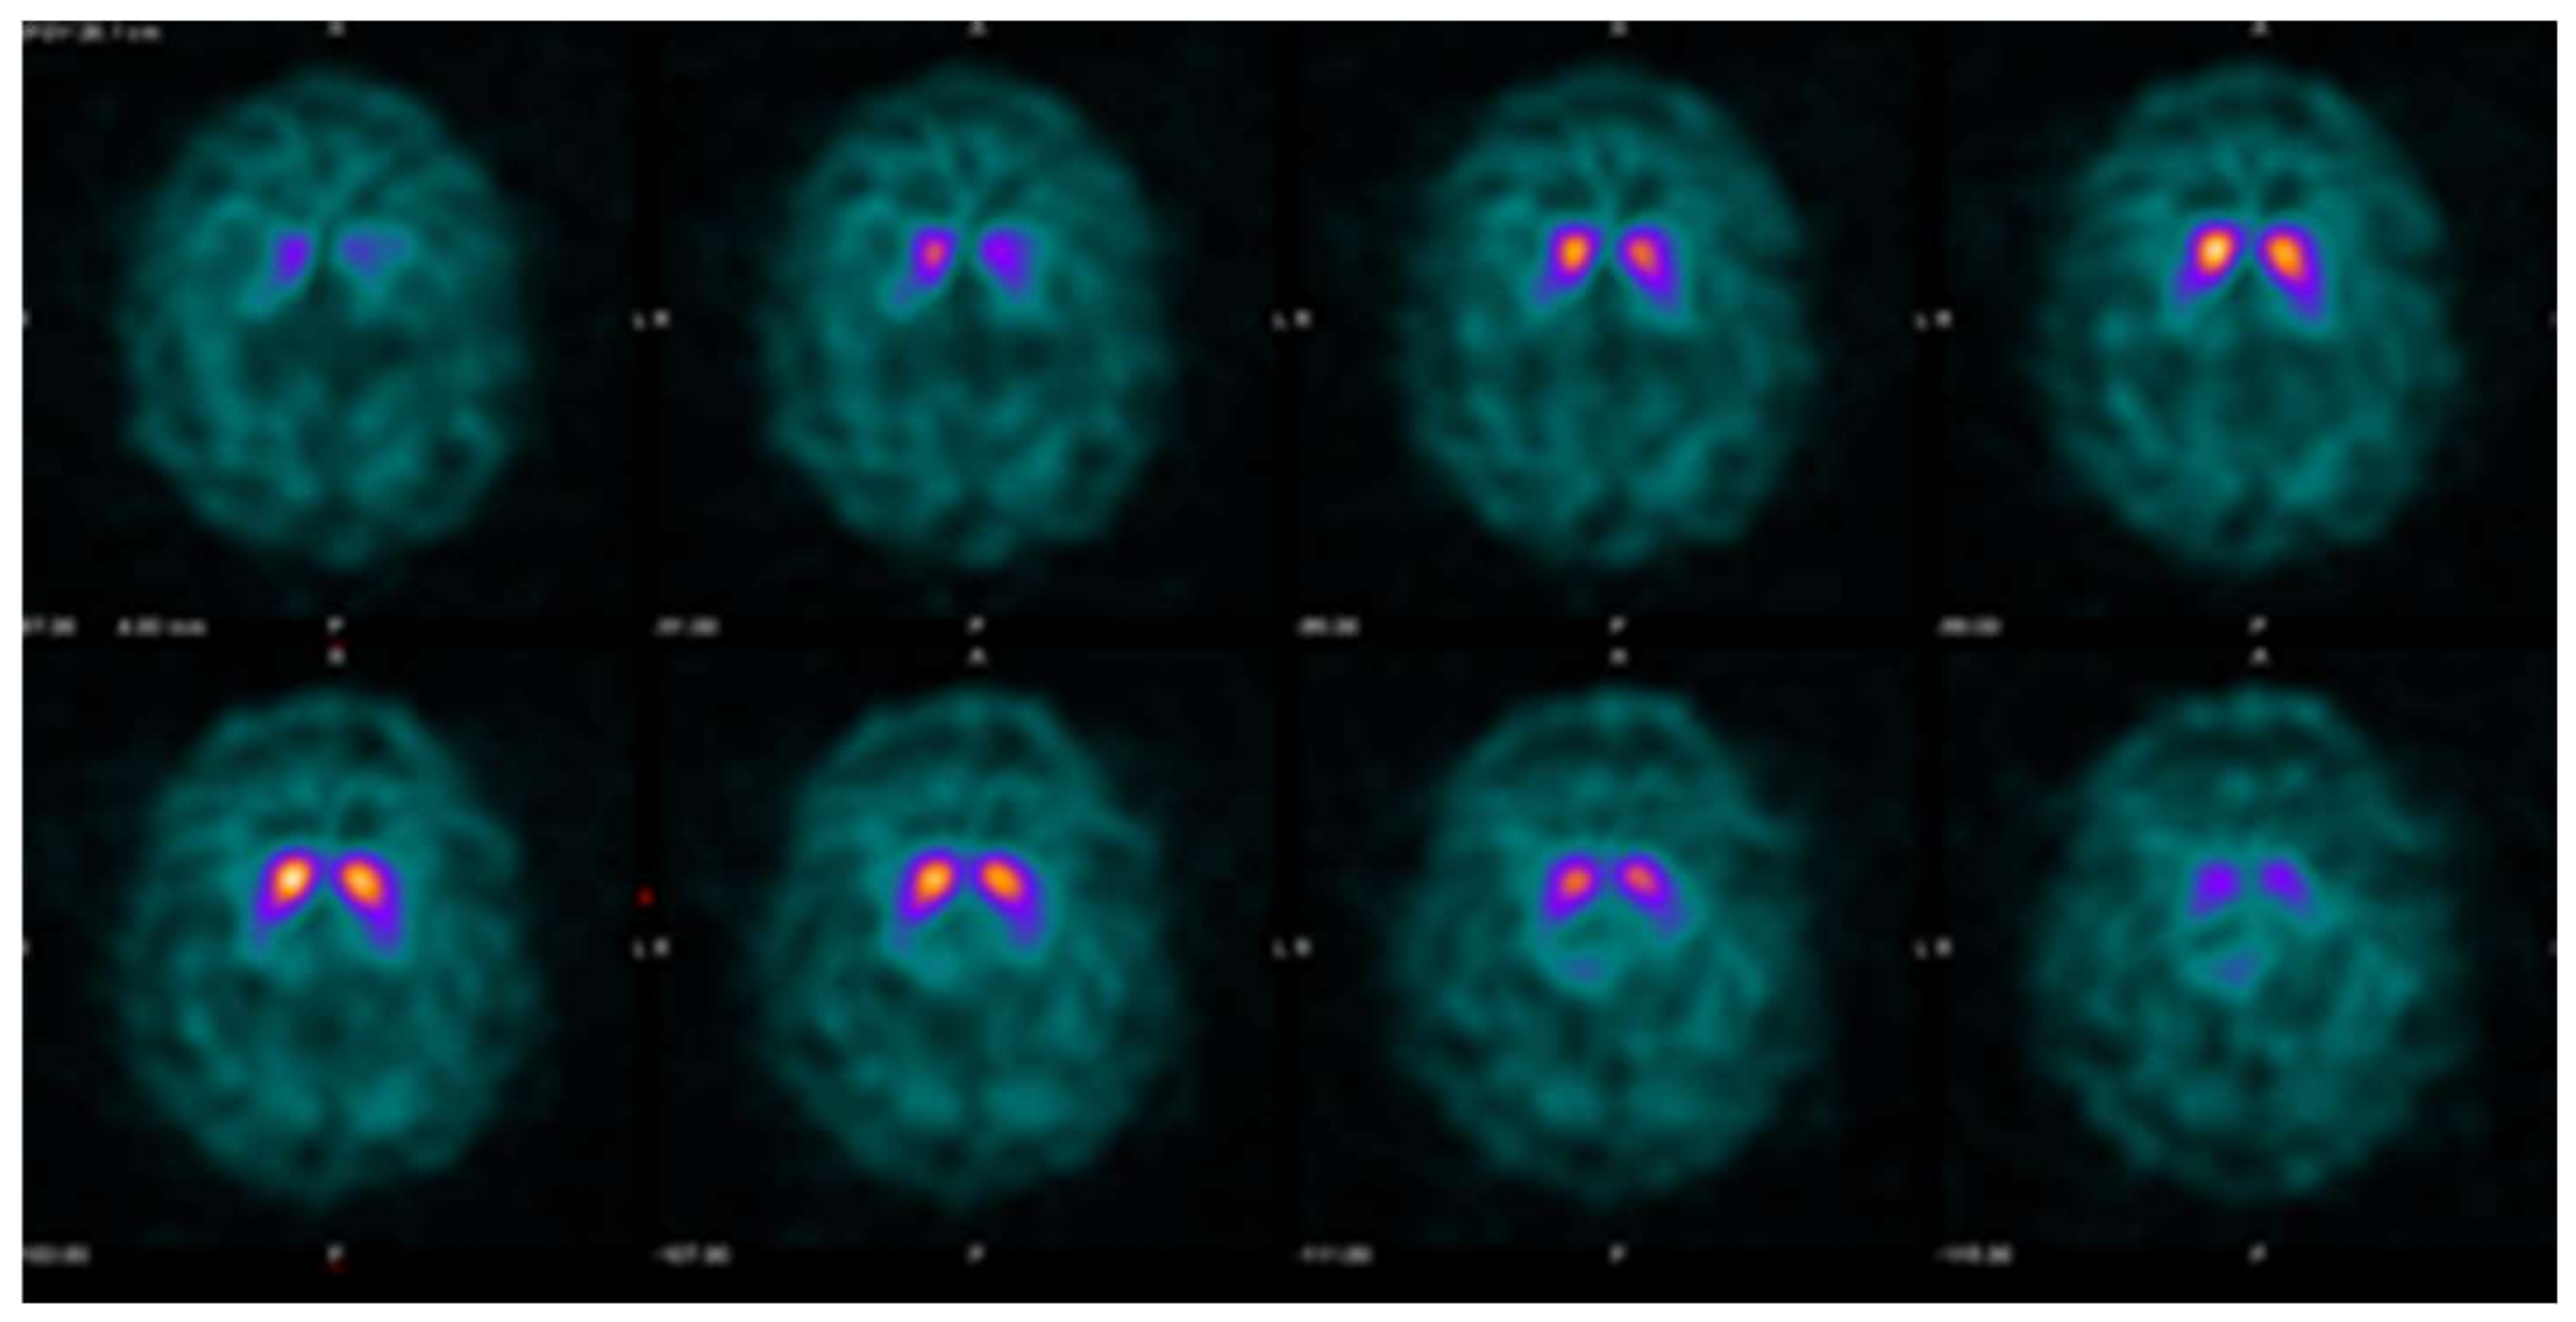

Figure 3.

Example DaTQUANT results in a non-PS patient demonstrating asymmetric loss of uptake within the left posterior putamen. Despite the asymmetry, none of the summary measures, SBR (1.39), z-score (−0.31), or percent deviations (−0.07) meet the threshold for abnormal.